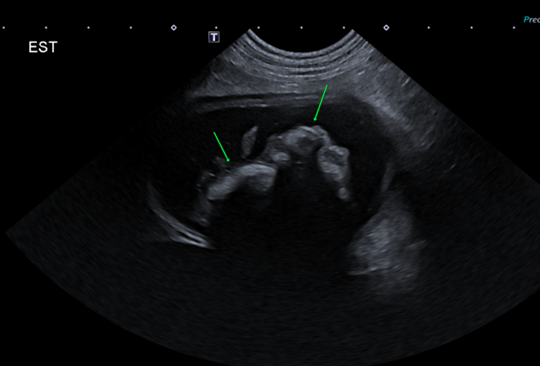

• L’intussusception peut également être secondaire : avec un péristaltisme augmenté et une obstruction mécanique, une anse peut s’invaginer dans une autre. L’aspect échographique est caractéristique, avec la visualisation d’une zone à double paroi digestive (intusseptum et intussuscipiens), à bien visualiser dans tous les plans pour éviter toute erreur d’interprétation.

Échographie abdominale : visualisation d’un corps étranger gastrique